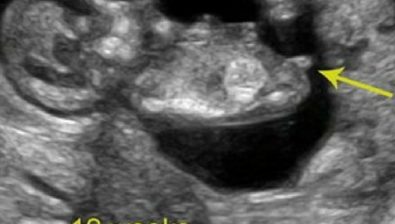

Ultrasound at 12 Weeks

The further along in your pregnancy, the more distinguished your baby’s heartbeat becomes.

At this point, you’re able to hear it by listening with a fetal doppler monitor. Your doctor will likely do this during each prenatal visit.

Your baby’s structures are all formed. From here on out, those structures will be growing at a rapid pace.

You’ll likely be able to see some movement on an ultrasound as your baby is wiggling and moving inside your uterus.